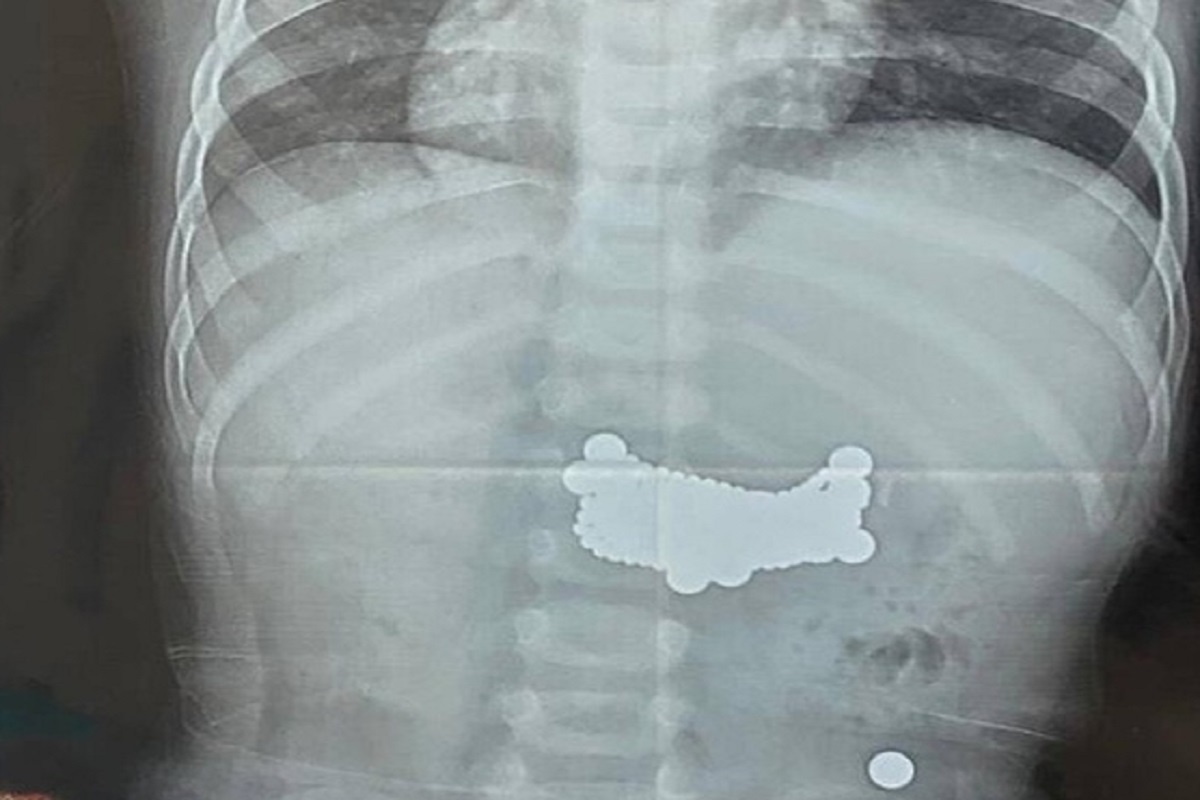

В Центре детской хирургии имени Л. М. Рошаля врачи в два этапа удалили 11 магнитов из желудочно-кишечного тракта 11-летнего мальчика. У ребенка начались осложнения в виде перфорации желудка. В Центр детской хирургии имени Л. М. Рошаля доставили 11-летнего мальчика, состояние которого поначалу связывали с возможной травмой на тренировке по самбо. Обследование показало, что причиной ухудшения здоровья стала не спортивная нагрузка, а тяжелая патология, вызванная наличием инородных предметов в организме. Во время томографического исследования врачи обнаружили множественные инородные тела, распределенные по всему желудочно-кишечному тракту. Как выяснилось в ходе дальнейшего осмотра, ребенок ранее проглотил 11 небольших магнитов. По данным медиков, эпизод произошел задолго до госпитализации, однако мальчик из-за стеснительности и страха не сообщил о случившемся родителям. Первые недели после проглатывания предметов выраженных жалоб не было, но затем у школьника появились боли в животе, тошно

Диагностика показала, что семь магнитов скопились в желудке, еще четыре продвинулись в тонкую кишку. За время нахождения в организме магниты успели сцепиться между собой и повредить стенку желудка, что привело к перфорации и потребовало немедленного оперативного вмешательства.